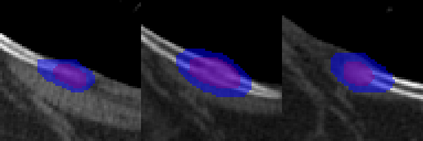

Rib fractures are a common and potentially severe injury that can be challenging and labor-intensive to detect in CT scans. While there have been efforts to address this field, the lack of large-scale annotated datasets and evaluation benchmarks has hindered the development and validation of deep learning algorithms. To address this issue, the RibFrac Challenge was introduced, providing a benchmark dataset of over 5,000 rib fractures from 660 CT scans, with voxel-level instance mask annotations and diagnosis labels for four clinical categories (buckle, nondisplaced, displaced, or segmental). The challenge includes two tracks: a detection (instance segmentation) track evaluated by an FROC-style metric and a classification track evaluated by an F1-style metric. During the MICCAI 2020 challenge period, 243 results were evaluated, and seven teams were invited to participate in the challenge summary. The analysis revealed that several top rib fracture detection solutions achieved performance comparable or even better than human experts. Nevertheless, the current rib fracture classification solutions are hardly clinically applicable, which can be an interesting area in the future. As an active benchmark and research resource, the data and online evaluation of the RibFrac Challenge are available at the challenge website. As an independent contribution, we have also extended our previous internal baseline by incorporating recent advancements in large-scale pretrained networks and point-based rib segmentation techniques. The resulting FracNet+ demonstrates competitive performance in rib fracture detection, which lays a foundation for further research and development in AI-assisted rib fracture detection and diagnosis.